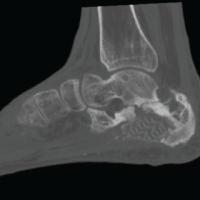

Patient was admitted and IV analgesics were given. Ultrasound of the abdomen and pelvis was done to rule out any internal organ injury, which was noted as normal. The patient was allowed full weight bearing and independent ambulation on the next morning and discharged (Fig. 4). Patient came for follow-up at 2 weeks, 1 month, 3 months, and 6 months. The patient continued to ambulate unassisted without any pain or limp. X-rays done were reported normal.